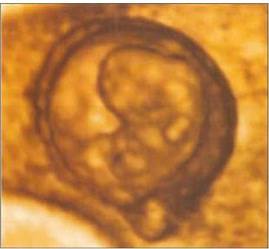

The head is now much larger in relation to the trunk and is more bent over the cardiac prominence. The trunck and neck have begun to straighten. Hand and foot plates are formed and digital or finger rays started to appear.3D ultrasound findings: During the 7th gestational week, spine gradually becomes visible, as well as limb buds, lateral to the body. Amnion can be seen as a spherical hyperechoic membrane, still close to the embryo. Chorion frondosum can be distinguished from the chorion leave. Fast development of rhombencephalon (hind-brain) occurs. This process gives even more prominence to the head. Head becomes the dominant embryonic structure. Using the multiplanar mode, developing vesicles of the brain can be depicted as anechoic structures inside the head. The biggest, and usually the only visible, is rhombencephalon placed on the top of the head (vertex). The head is strongly flexed anterior being in contact with the chest. The hypoechogenic brain cavities could be identified, including the separated cerebral hemispheres. The lateral ventricles are shaped like small round vesicles. The cavity of the diencephalon (future third ventricle) runs posterior. In the smallest embryos, the medical telencephalon forms a continuous cavity between the lateral ventricles. The future foramen of Monro are wide. In the sagittal plane, the height of the cavity of the diencephalons (future third ventricle) is slightly greater than that of the mesencephalon. Thus, the wide border between the cavities of the diencephalon and the mesencephalon is indicated. The curved tube-like mesencephalic cavity (future sylvian aqueduct) lies anterior, its rostral part pointing caudal. It straightens considerably during the following weeks.

Besides the aorta and umbilical blood flow, at the end of 7th week, 3D power Doppler depicts features of early vascular anatomy on the base of the skull. Vessels are evolving laterally to the mesencephalon and cephalic flexure. Apart from embryonic ciculation, 3D power Doppler can obtain blood flow signals from the intervillous space. The gestational sac occupies about one-third of the uterine volume. The main landmark now is an echogenic fetal pole consisting of embryo adjacent to a cystic yolk sac. The intracranial circulation becomes visble during the seventh week of gestation. At this time, discrete pulsations of the internal carotid arteries are detectable at the base of the skull.